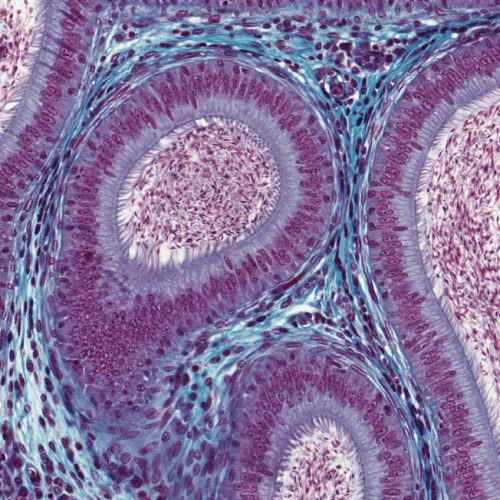

A histopatologia é o exame microscópico de tecidos biológicos para o diagnóstico de doenças, sendo o diagnóstico definitivo (“padrão ouro”) para a maioria dos processos.

O exame histopatológico envolve o exame de uma biópsia (ou seja, uma amostra retirada cirurgicamente por um médico veterinário) e analisado por um médico veterinário especializado, chamado patologista.